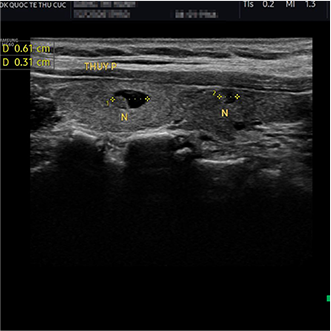

VABB (Vacuum-Assisted Breast Biopsy) là phương pháp điều trị u vú lành tính ứng dụng công nghệ cao. Bác sĩ sử dụng máy sinh thiết dao cắt quay dưới hướng dẫn của siêu âm để cắt và hút bỏ u ra ngoài qua lõi kim được chọc qua da thông qua một vết rạch siêu nhỏ khoảng 3-5mm để tiếp cận vị trí có khối u. Nhờ cơ chế hút liên tục, mô u được lấy ra chính xác, trọn vẹn mà không làm tổn thương mô lành xung quanh.

Phương pháp chỉ tạo một nốt chích nhỏ trên da, hạn chế xâm lấn, không cần khâu da, giúp vết thương nhanh lành và đảm bảo thẩm mỹ vùng ngực.

Khối u có chỉ định ngoại khoa có kích thước nhỏ hơn hoặc bằng 3cm.

Khối u >3cm, bệnh nhân sờ thấy khó chịu, gây biến dạng gồ ghề, mất thẩm mỹ.

Một số trường hợp khối u nhỏ hơn hoặc bằng 1cm ảnh hưởng chất lượng cuộc sống.